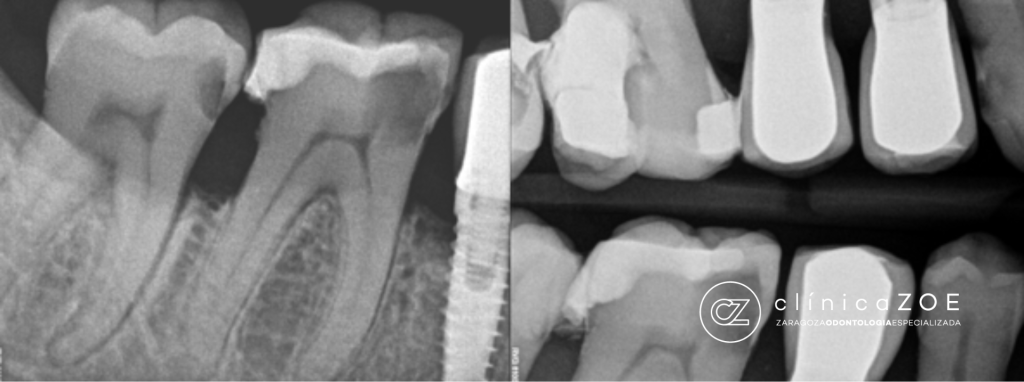

- Exploración detallada: buscamos desgastes cervicales, recesión, fracturas, caries, restauraciones filtradas.

- Radiografías y fotografía macro para ver microdetalles.

Si hay caries, fisuras profundas o inflamación pulpar, realizamos empaste, incrustación, corona o endodoncia según el caso.